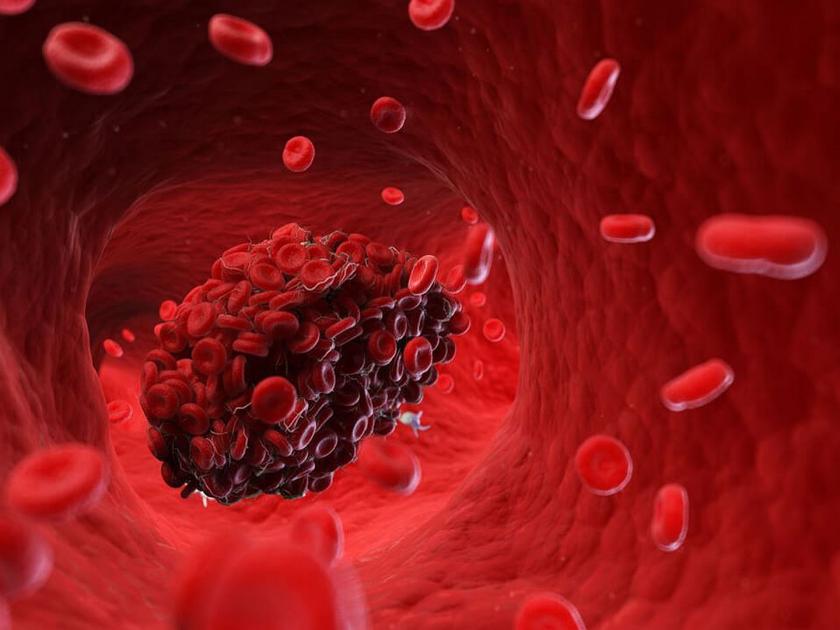

शरीरात व्हिटॅमिन K ची कमतरता सामान्य बाब नाही. याची खासियत म्हणजे फार रेअर केसमध्ये या व्हिटॅमिनची शरीरात कमतरता होते, पण जेव्हा होते तेव्हा हे कोणत्या ना कोणत्या गंभीर आजाराचं कारण ठरतं. या व्हिटॅमिनच्या कमतरतेमुळे रक्ताच्या गाठी तयार होणं वाढतं. याने जीवाला धोका होऊ शकतो. तसेच रक्त पातळ होऊ लागतं. अशात जखम झाली किंवा ब्रेन हॅमरेज झाल्यावर रक्त अधिक वाहू लागतं.

शरीरात नाही होत तयार

आपल्या शरीरासाठी जास्तीत जास्त आवश्यक गोष्टी निर्मित करण्याची क्षमता शरीरातच असते. पण व्हिटॅमिन K मिळवल्याशिवाय आपलं शरीर प्रोथोम्बिनची निर्मिती करू शकत नाही. जे शरीरातून निघणाऱ्या रक्ताच्या क्लोटिंगसाठी गरजेचं आहे. त्यासाठी नियमितपणे हिरव्या भाज्या, दूध, ड्राय फ्रूट्स आणि फळांचा आहारात समावेश करावा.